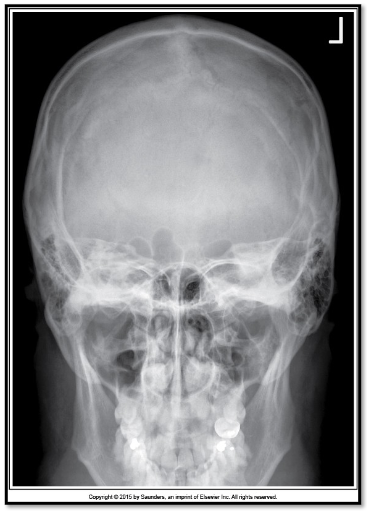

Q

what should be corrected about the petrous ridges in this PA cadwell

A

nothing!

what are the corrections for this PA caldwell (3)

CP needs to be raised

nose to go right slightly

vertex to go left